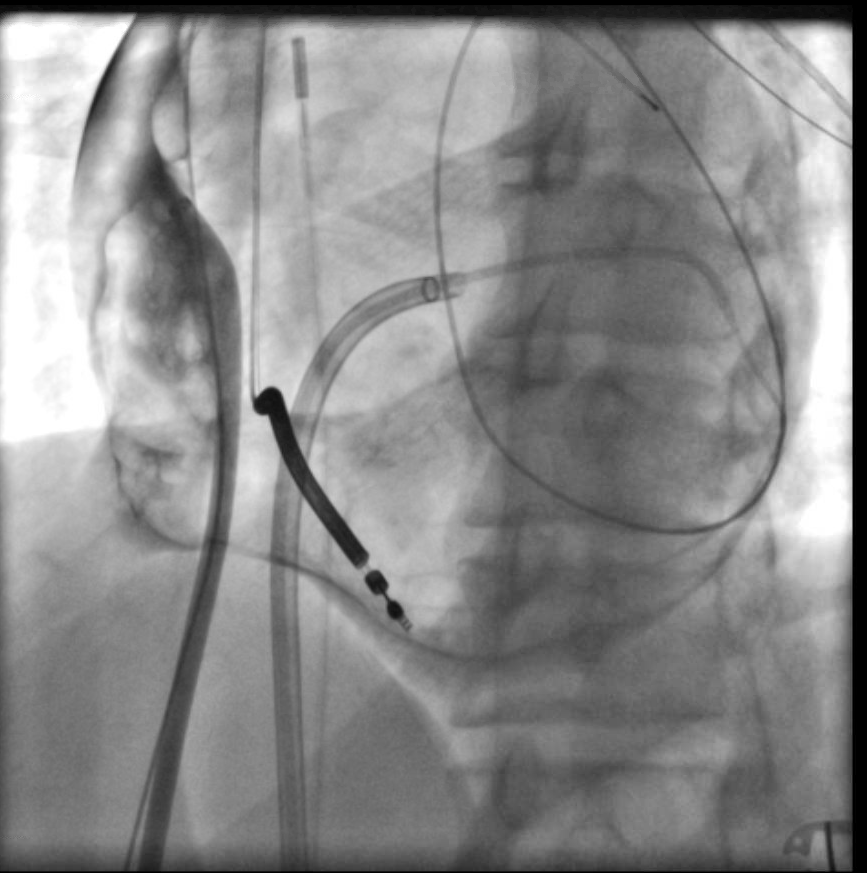

Example of inHEART for epicardial access planning. Young patient with small thorax, not much space between LIMA and sternum. More medial needle approach used. CO2 insufflation for added safety. Fluoro shot is in LAO (didn't save AP)! Inferolateral epi VT ablated. #EPeeps

Example of  <a href="/inheartmedical/">inHEART</a> for epicardial access planning. Young patient with small thorax, not much space between LIMA and sternum. More medial needle approach used. CO2 insufflation for added safety. Fluoro shot is in LAO (didn't save AP)! Inferolateral epi VT ablated. #EPeeps

inHEART (@inheartmedical) 's Twitter Profile Photo

Congratulations to Dr. Esseim Sharma, MD, FHRS on this exceptional #epicardial access case! Find out how inHEART can help you plan a safe epicardial approach by incorporating surrounding structures at inheartmedical.com #inHEART #Epeeps